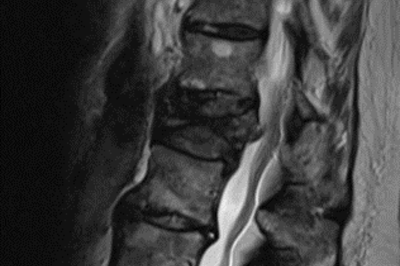

• Wirbelsäulenfraktur nach Sturz

Röntgenbild Fraktur nach Sturz bei Osteoporose

Nicht verheilte Fraktur nach Sturz bei Osteoporose